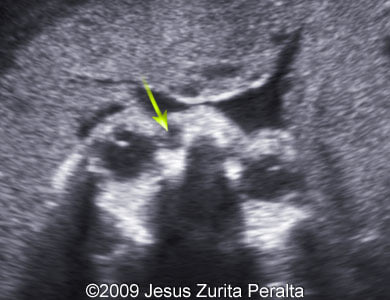

The following images show a case of the dacryocystocele diagnosed at 30 weeks of a pregnancy.

Images 1, 2: 30 weeks; the image 1 demonstrates a transverse scan of the fetal face at the level of the fetal orbits with the dacryocystocele (arrow) localized in the left canthus. The image 2 demonstrates a fusion of the image 1 and a drawing explaining the position of the fetal head and location of the dacryocystocele (arrow).